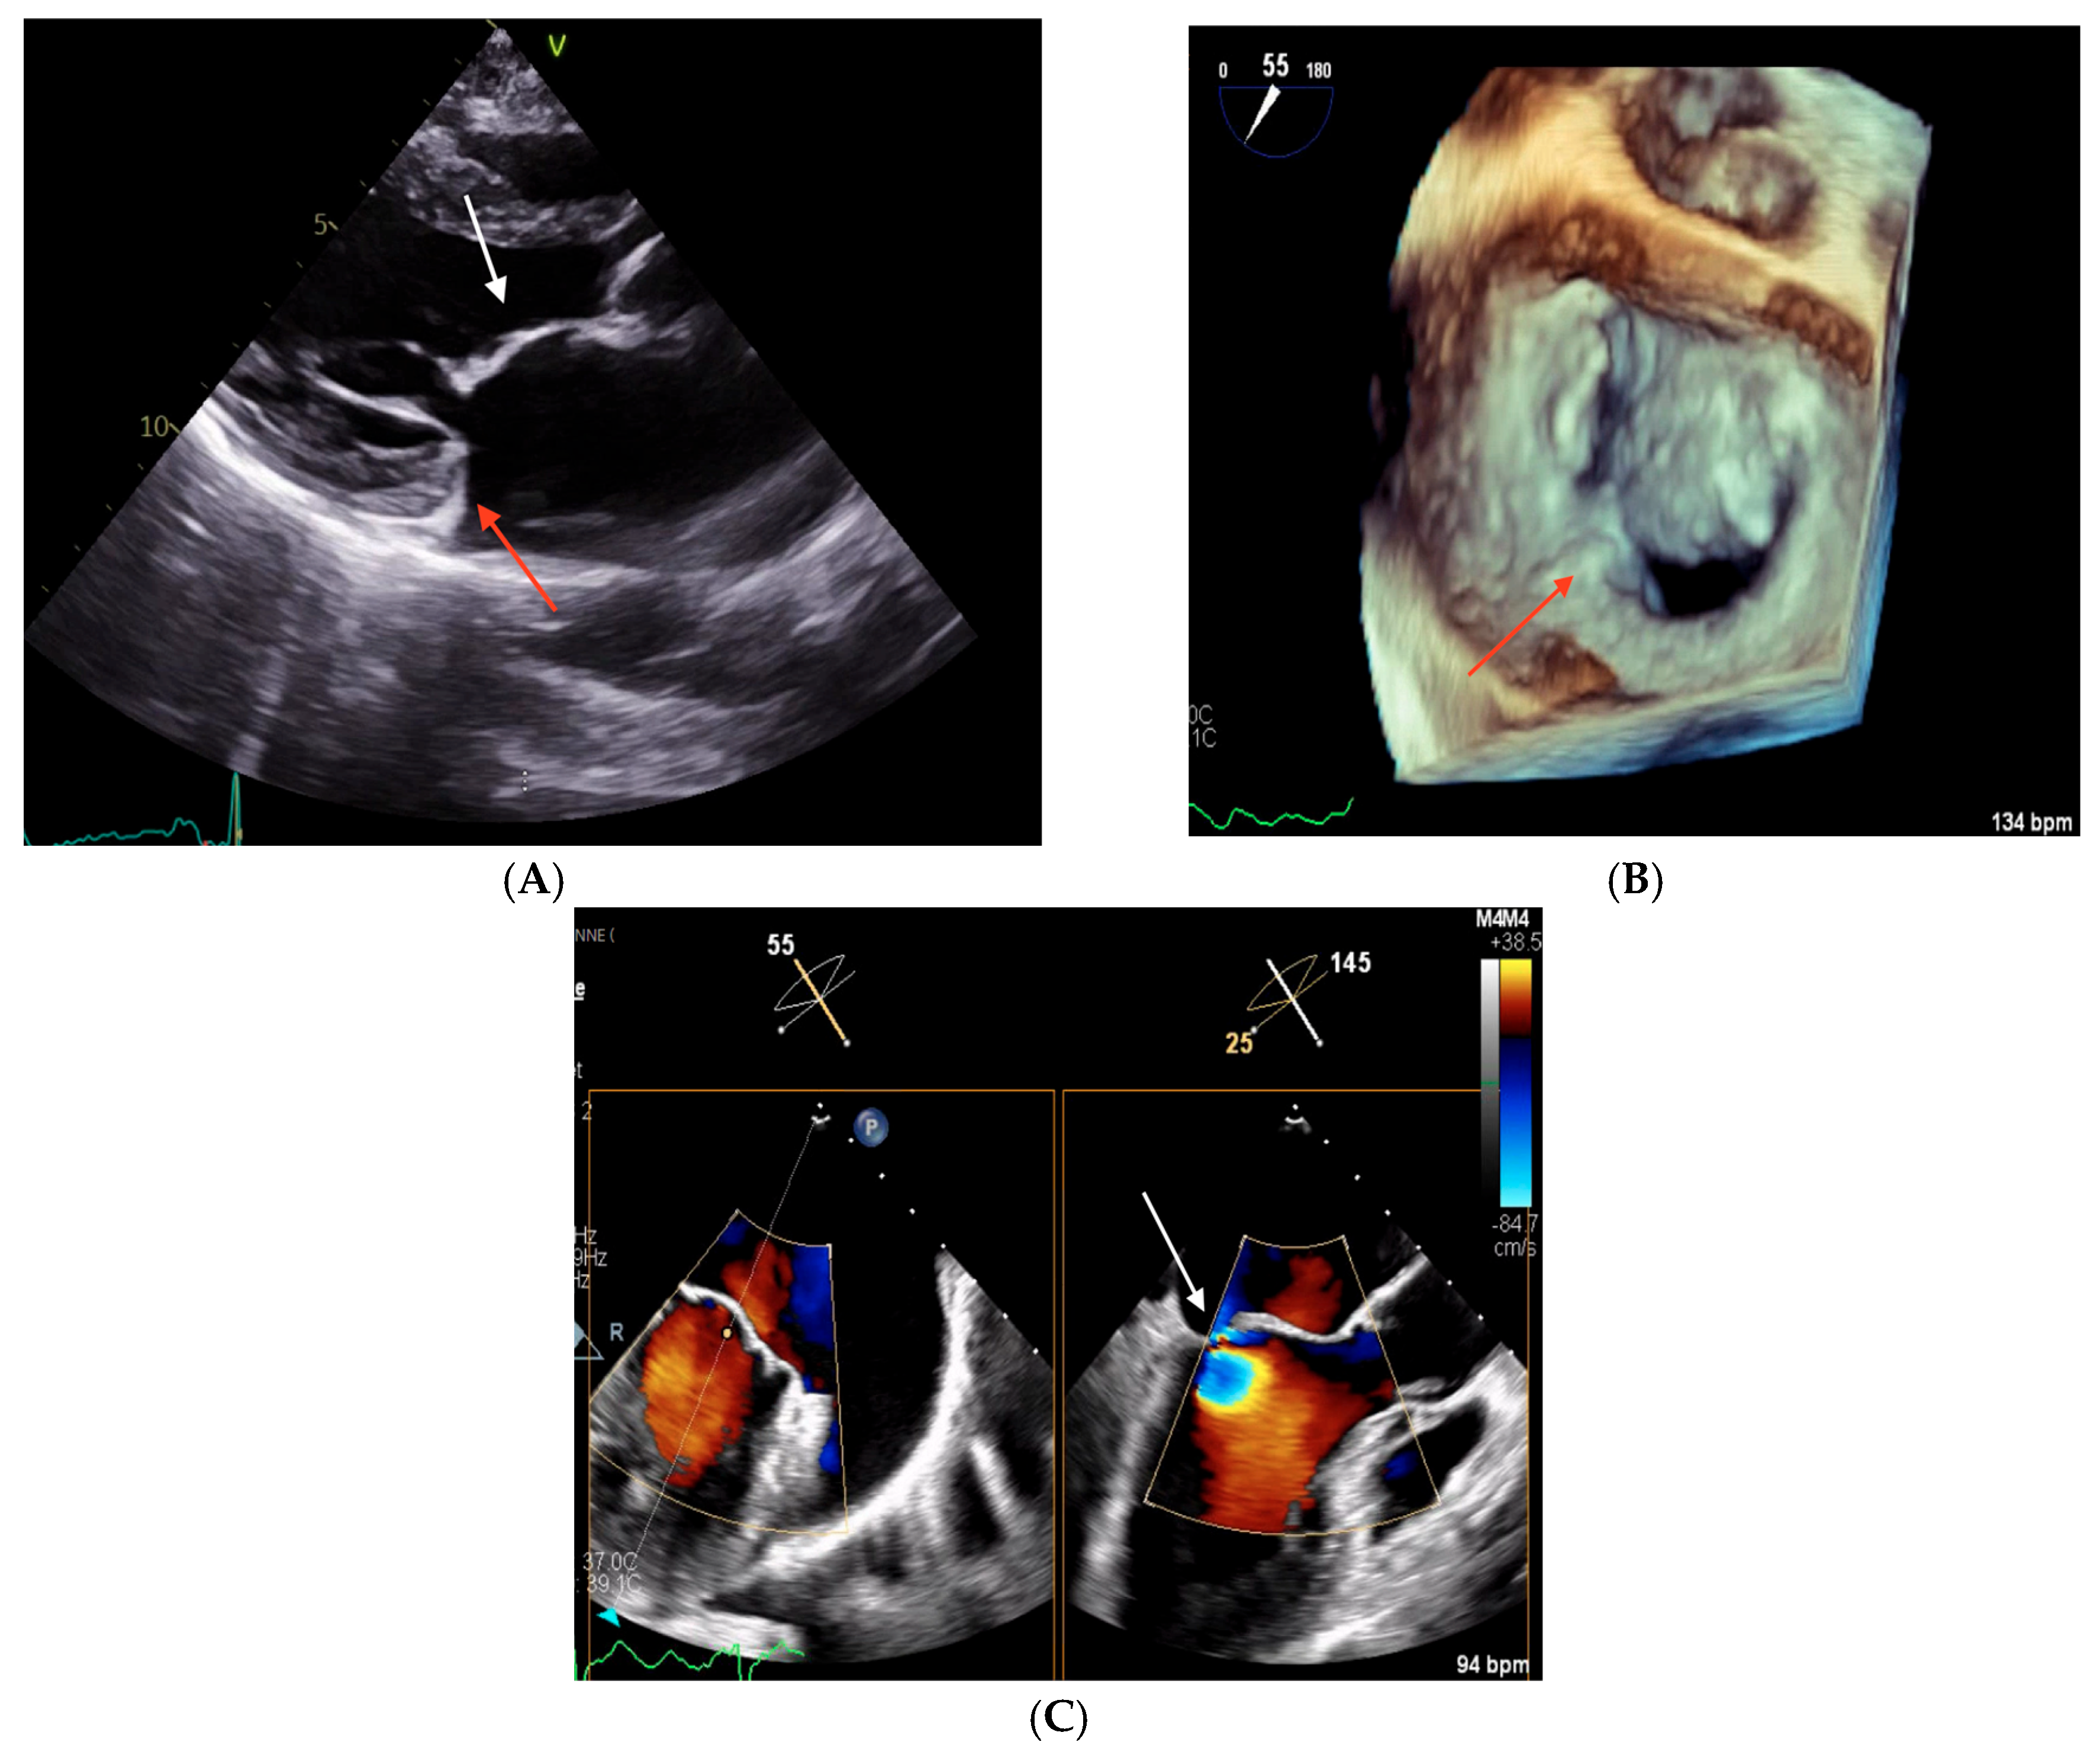

2.2. Clinical Case 2